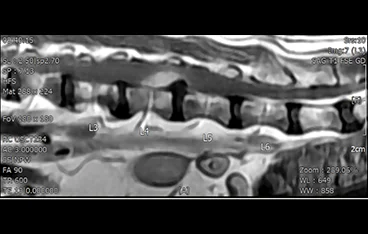

• 경추 디스크 MRI

• 흉요추 디스크 MRI